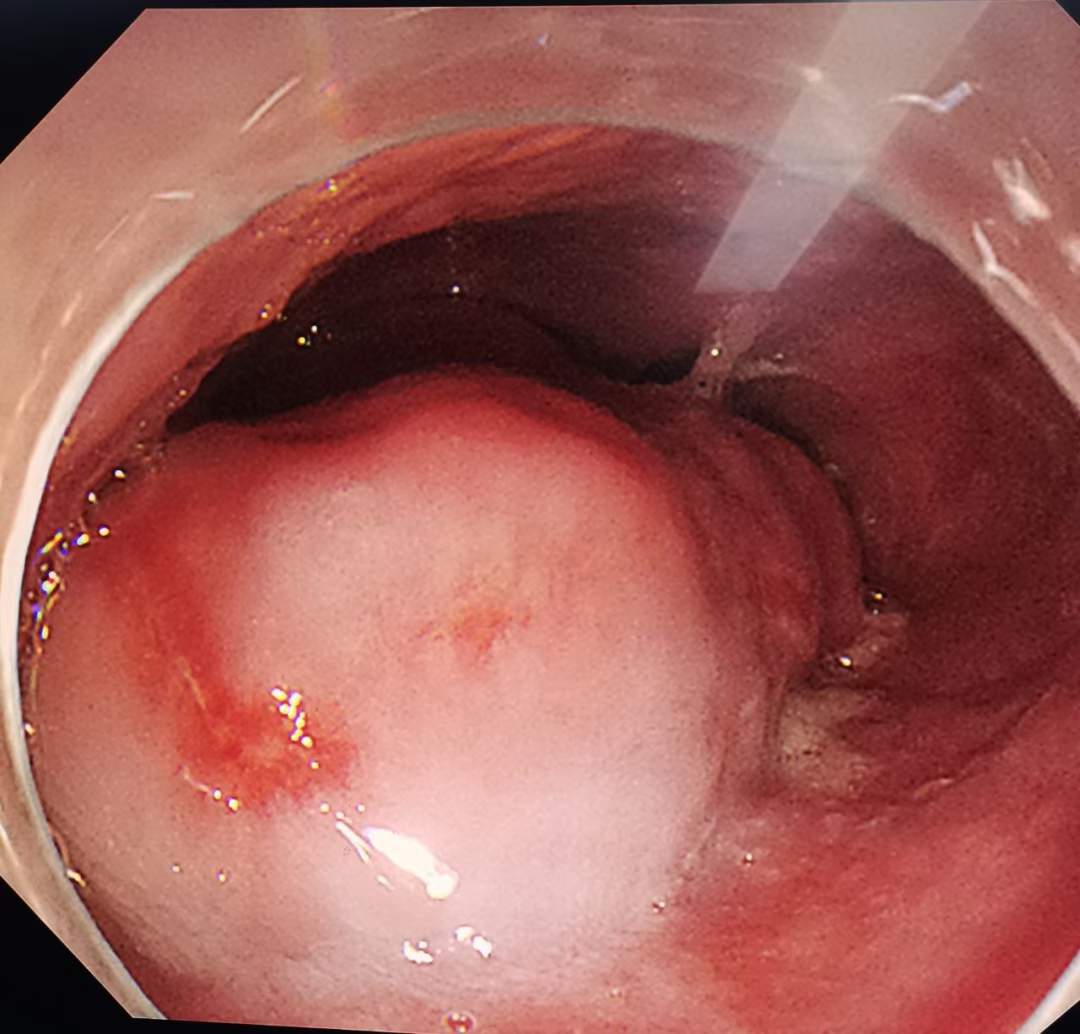

患者,男,58岁,主因“间断进食不畅1月”,就诊于我消化内三科。我院电子胃镜提示:食管下段近贲门处可见巨大隆起性病灶,超声内镜提示:病变起源于固有肌层,最大切面大小约4cmx1.3cm,呈低回声。考虑平滑肌瘤。积极完善相关化验及检查,查无内镜下治疗禁忌症,遂于2023年5月30日行内镜下食管肿物挖出术。

术后病检提示:(食管下段)平滑肌瘤,肿瘤大小5x2.3x2cm;

免疫组化结果显示:CD117(-),CD34(部分细胞+),Desmin(+),DOG1(-),Ki-67(阳性率≈1%),S-100(-),SDHB(-),SMA(+)。

内镜下的“爪子”让粘膜下巨大肿物不再继续作怪!